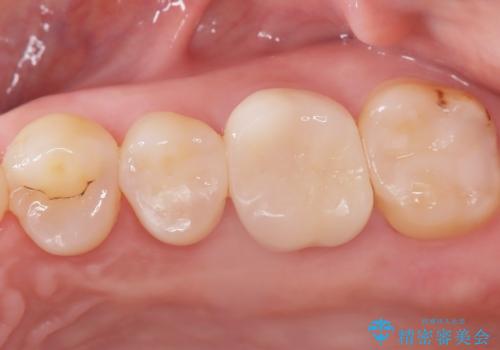

2回で完了した奥歯のセラミック修復

今回の治療では、虫歯の大きさや深さに応じて、異なるセラミック修復法を適用しました。

比較的軽度な虫歯には、セラミックインレー(詰め物)で対応し、健全な歯質を最大限に残しました。

進行した虫歯や歯の強度が低下している歯には、セラミッククラウン(被せ物)を選択し、歯全体を保護することで破折を防ぎました。

短期間での治療を可能にしつつ、天然歯と見分けがつかない審美性と、長期的に安定する機能性を兼ね備えたセラミック修復を実現しました。